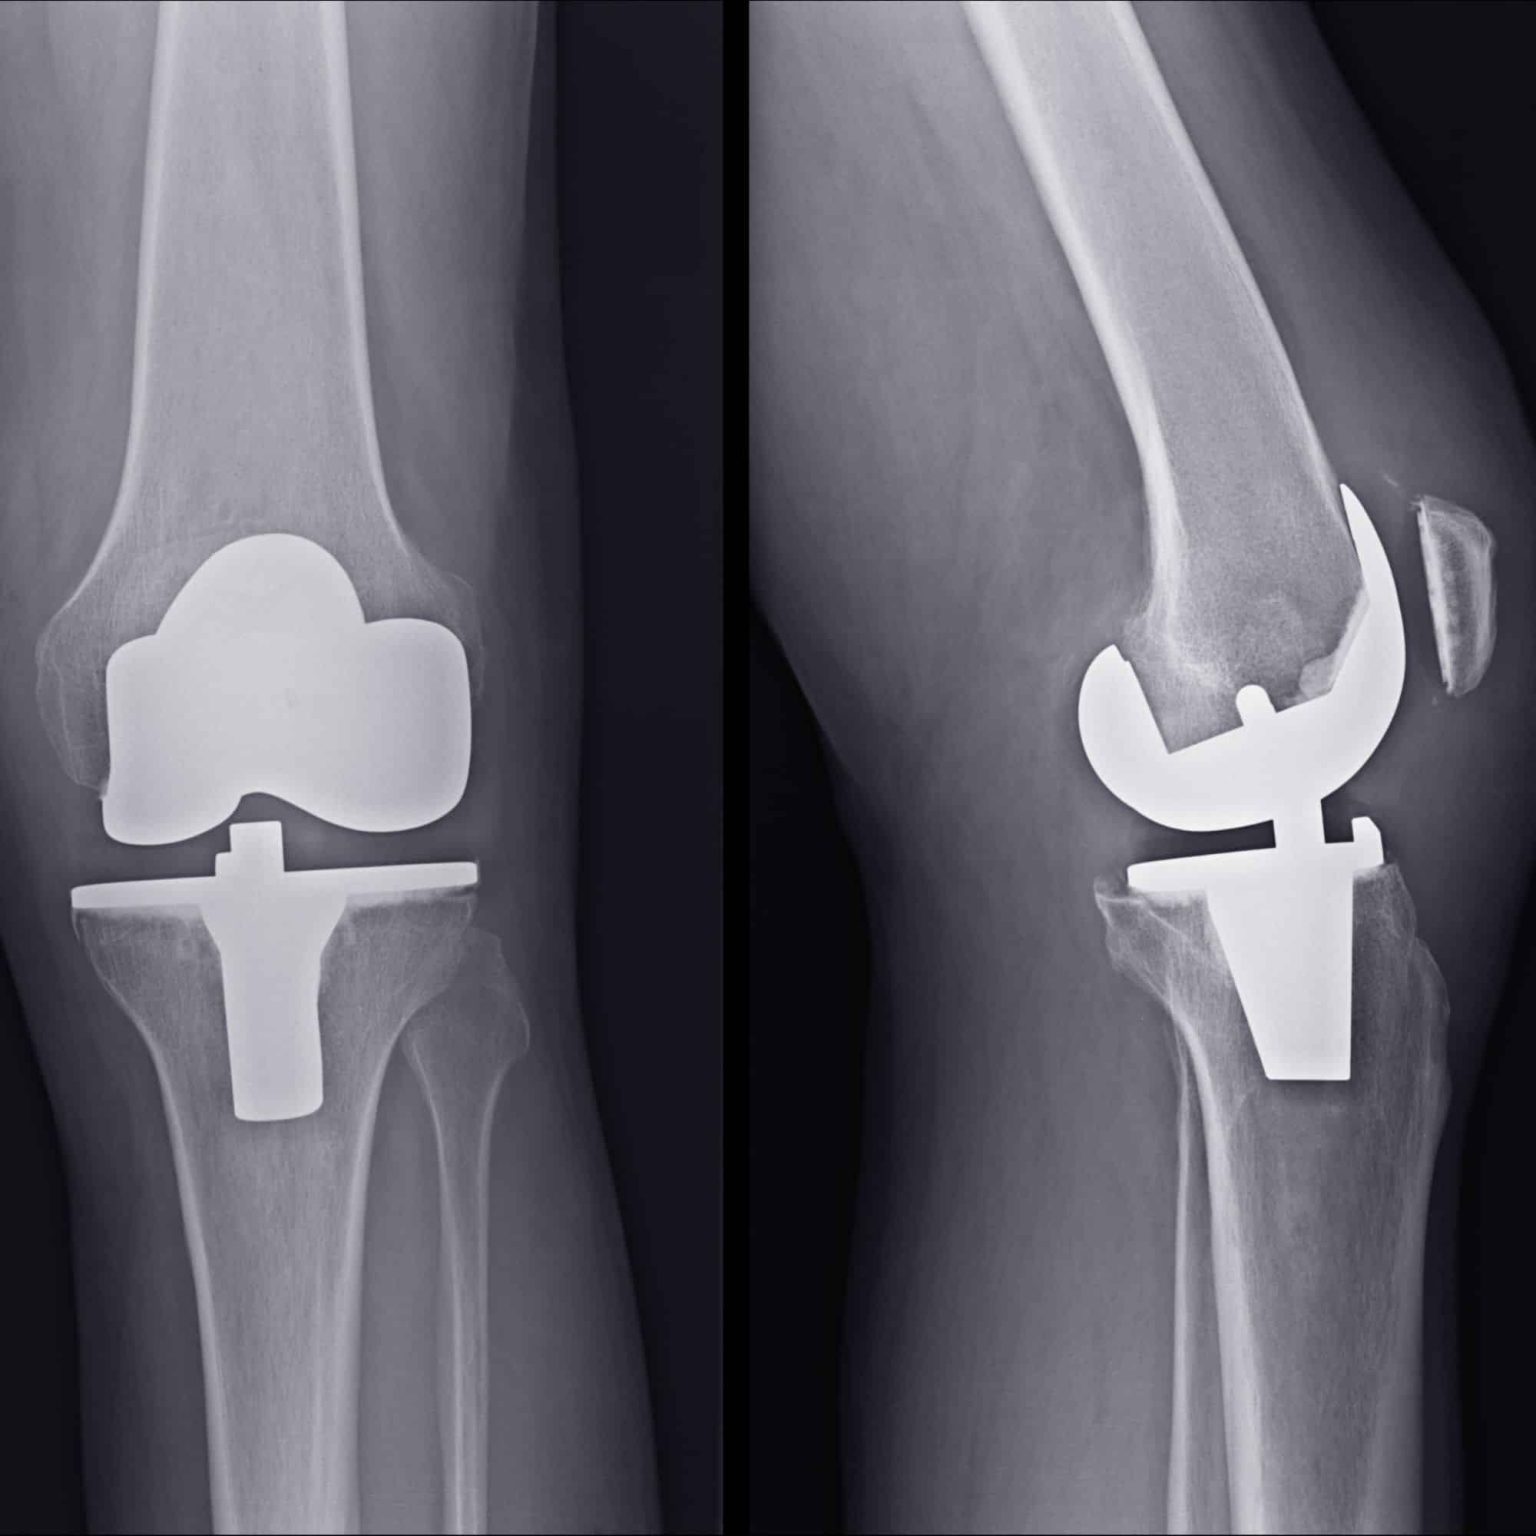

Knee replacement, or knee arthroplasty, is a surgical procedure where a damaged or arthritic knee joint is replaced with a prosthetic implant. This procedure is recommended for individuals suffering from chronic knee pain due to arthritis, sports injuries, or degenerative conditions. Dr. Lokesh Yogi and his team at Jaipur Ortho are leaders in minimally invasive knee replacement surgery, offering precise treatment plans for faster recovery and long-term success.

- Total Knee Replacement (TKR): Replacement of the entire knee joint.

- Partial Knee Replacement (PKR): Replacement of only the affected compartment.